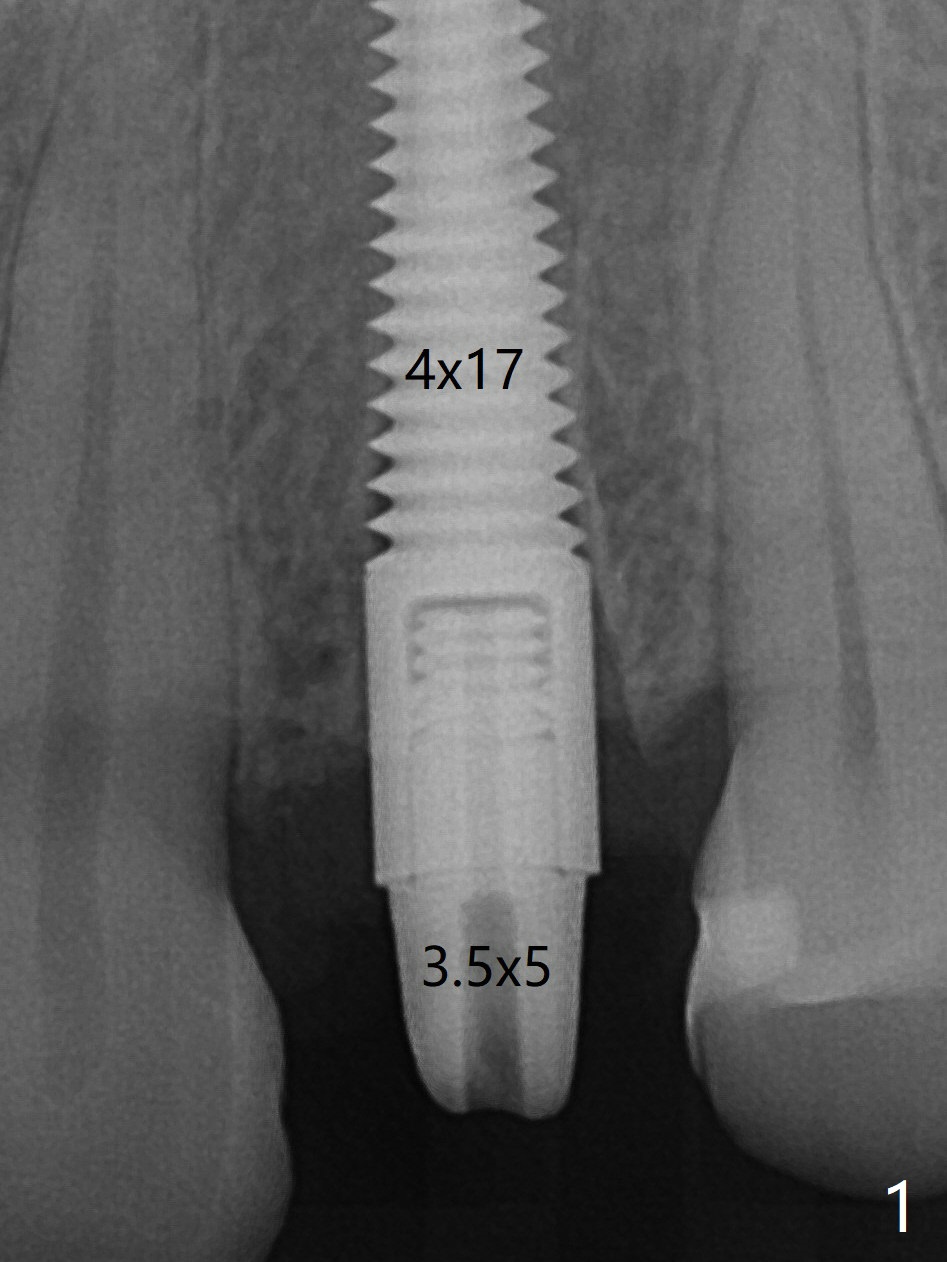

Since there is no buccal plate atrophy at 4, or 8, socket shield is not attempted at #13. Extraction turns out to be difficult because of tooth fracture. The buccal and palatal flaps have to be elevated minimally for tooth sectioning and purchase point formation. More surprising, a 4.5 mm implant appears to be too wide for the space; a 4x17 mm implant achieves insertion torque >60 Ncm (Fig.1,2). Because of the seal with the immediate provisional, the bone graft remains in place 1 month postop (Fig.5). There is no bone loss 5.5 months postop (Fig.6,7) or 6.5 months postop (immediately post cementation, Fig.8).